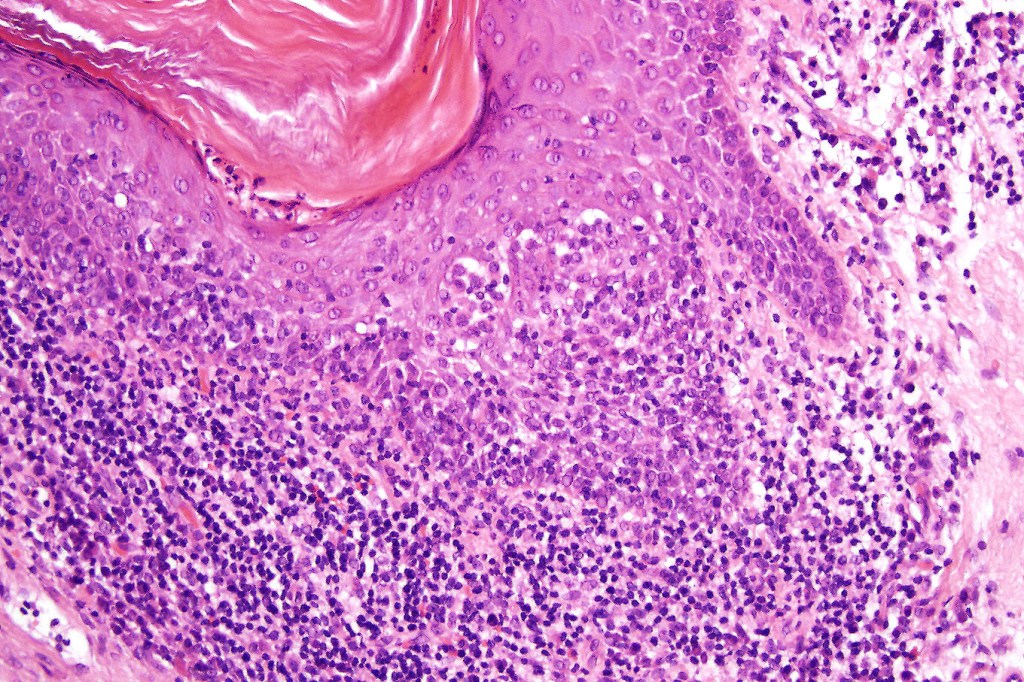

Histological features

•Epidermal involvement often absent

•Follicular infiltration by atypical lymphocytes & Sézary cells

•+/- basaloid follicular hyperplasia

•Granulomatous inflammation secondary to follicular destruction